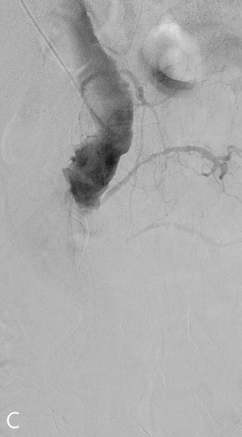

Fig 2C

(C) Angiogram of the false lumen was obtained to evaluate the extent of dissection and relationship of the intimal flap.

Fig 2D

(D) Angiogram of the true lumen via femoral access showed the luminal narrowing of true lumen at infrarenal level and mesenteric arteries were arising from true lumen.

Fig 2E

(E) Fenestration from true lumen to false lumen was performed using transseptal needle under the ultrasound guidance.

Fig 2F

(F, G) Abdominal ultrasound transverse and longitudinal view demonstrated the aortic dissection and guide the fenestration.

Fig 2G

Fig 2H

(H) After puncture, serial balloon dilatation was performed upto 25mm in diameter.

Fig 2I

(I) Final aortography showed even contrast flow at both true and false lumen, which meant the technical success of aortic fenestration.